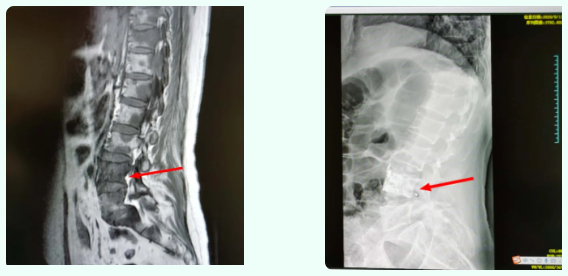

术前MRI示多个椎体转移,L4明显骨质破坏(左图),术后可见骨水泥填充完好。放疗结束后患者疼痛症状明显缓解,生活质量明显改善。